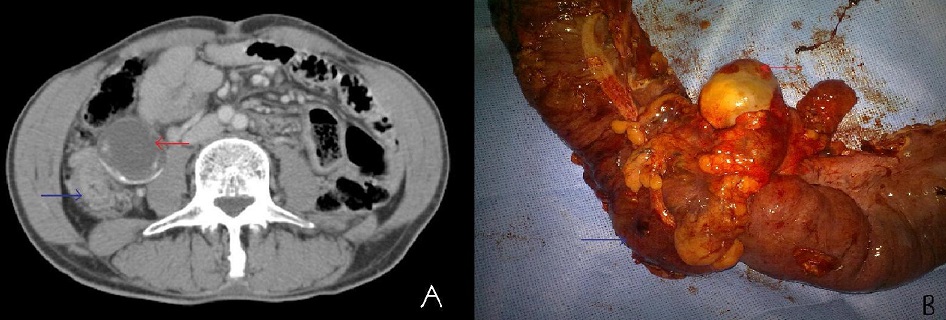

Le mucocèle appendiculaire est une lésion rare de l’appendice caractérisée par l’accumulation de mucus dans la lumière appendiculaire occasionnant une dilatation de la lumière appendiculaire. Sa pathogénie est controversée, deux théories physiopathologiques ont été développées : une théorie obstructive et une théorie néoplasique. L’obstacle peut être: une tumeur endocrine appendiculaire, non sécrétante, adénome ou adénocarcinome du cæcum ou de l’appendice, endométriose, compression extrinsèque par des nodules de carcinose péritonéale, infections spécifiques : stercolithe, corps étrangers, volvulus appendiculaire ou plicature, diverticule appendiculaire. Nous rapportons l’observation d’un patient âgé de 55 ans qui a présenté depuis 08 mois un syndrome subocclusif à répétition spontanément résolutif associé à une douleur abdominale localisée au niveau de la fosse iliaque droite avec notion d’amaigrissement chiffré à 8 Kg. L’examen clinique a mis en évidence une sensibilité au niveau de fosse iliaque droite sans masse palpale. Une Coloscopie réalisée a mis en évidence un processus bourgeonnant coecal. L’examen anatomopathologique de la biopsie est revenu en faveur d’un adénocarcinome bien différencié et infiltrant. Le scanner thoraco-abdomino pelvien a révélé un épaississement irrégulier du coecum et de la dernière anse iléale associé à une formation kystique latéro coecale interne faisant suspecter un mucocele appendiculaire. Le patient a été opérer par laparotomie mediane avec découverte en per opératoire d’une masse coecale dure associée à un mucocèle appendiculaire d’où la réalisation d’une hémicolectomie droite avec anastomose iléo colique término terminale. L’examen anatomopathologique de la pièce opératoire a mis en évidence un adénocarcinome colloïde muqueux du coecum circonférentiel arrivant jusqu'à la sous séreuse. Les limites de résection distale et proximale ont été saines. Présence de 12 nodules tumoraux dans la sous séreuse, engainement perinerveux, et d’un mucocéle appendiculaire. Le curage ganglionnaire a comporté 10 ganglions non métastatiques .La tumeur a été classée pT3N1C. Les suites opératoires ont été simples. Le patient a été adressé en oncologie pour chimiothérapie adjuvante après réunion de concertation multidisciplinaire. Sur un recul de 09 mois, pas de récidive locorégionale ni de métastase à distance.